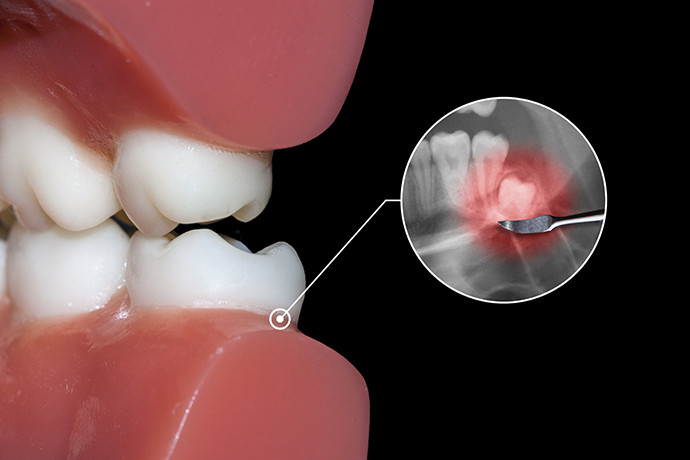

ถ้าไม่ถอน "ฟันคุด" เราจะต้องดูแลและรักษามันอย่างไร ?

เป็นเรื่องปกติสำหรับการมีฟันแท้ที่ขึ้นครบตามจำนวนฟัน 32 ซี่ คนที่กังวลว่า มีฟันคุดหรือเริ่มมีอาการเจ็บ และโดยเฉพาะ คนที่กำลังจะต้องจัดฟัน จะทำอย่างไรเมื่อเราอยากเก็บมันไว้แทนการถอนออก

กรณีที่ต้องผ่าฟันคุดเกิดจากฟันคุดอยู่ลึกลงไปใต้เนื้อเยื่อของเหงือก หรือฟันงอกขึ้นมาบางส่วนแต่มีลักษณะนอน ไม่ตั้งตรง ไม่สามารถดึงขึ้นมาได้ กรณีนี้ทันตแพทย์มักใช้วิธีผ่าเหงือก และอาจมีการตัดผ่าแบ่งฟันออกเป็นชิ้นเล็กๆ แล้วค่อยคีบนำฟันออกมาจากเบ้าฟัน

ฟันคุดแบบมีเหงือกปกคลุม

- ต้องผ่าตัดเอาฟันคุดออกและเย็บแผล อาการไม่ได้น่ากลัวมากนัก เพราะฟันคุดใกล้จะขึ้นแล้ว แต่ถ้าไม่ปวดรุนแรง ก็สามารถรอให้ฟันคุดขึ้นเต็มที่ก่อนได้